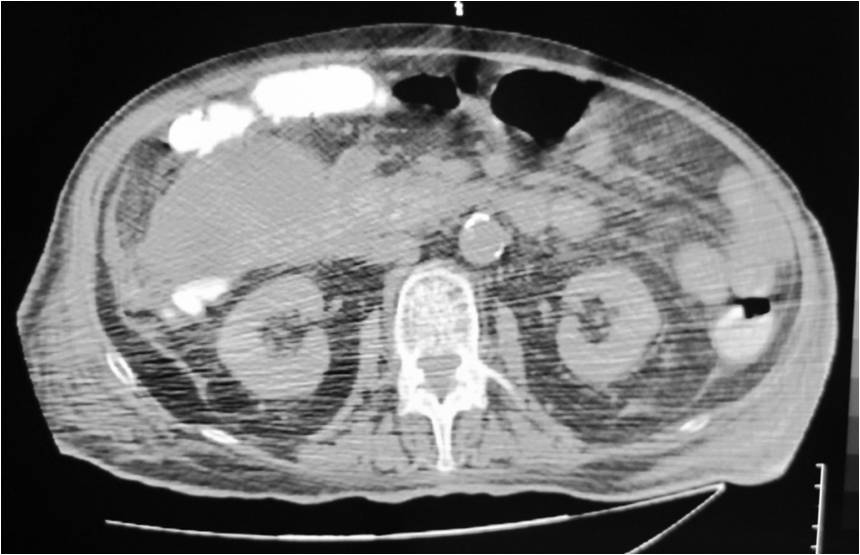

- Large abdominal abscess post- pancreatic surgery

- Successful drainage